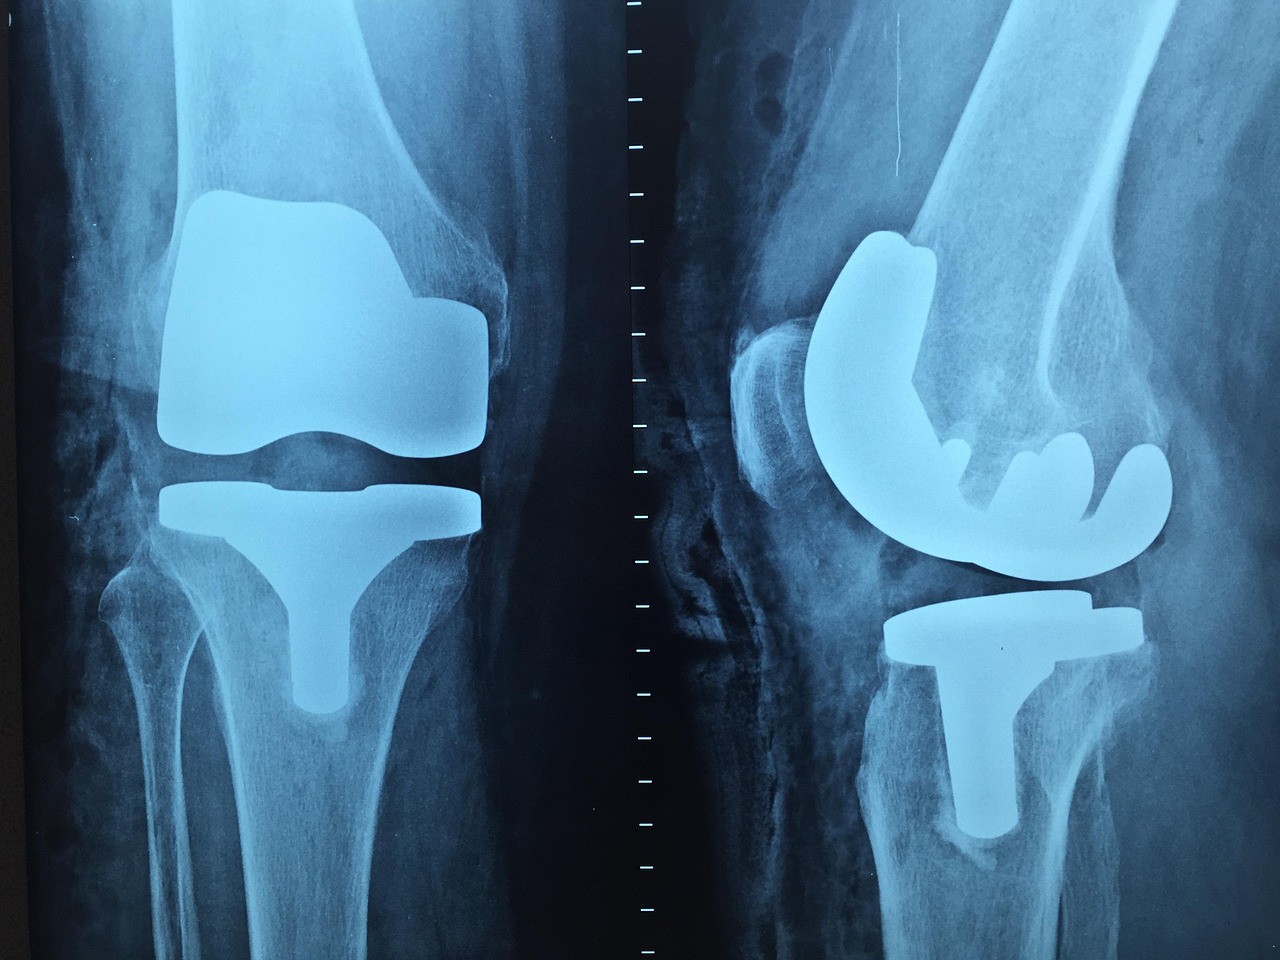

몸속을 들여다보게 한 X-레이

1895년, 독일의 물리학자 빌헬름 뢴트겐은 전혀 의도치 않게 사람의 뼈를 볼 수 있는 방법을 발견했어요. 그게 바로 X-레이! 실험 중 이상한 형광 빛을 포착한 그는 이 빛이 물체를 투과한다는 사실을 알게 되었고, 결국 자신의 아내 손을 촬영해 인류 최초의 X-레이 사진을 남겼죠. 이후 X-레이는 의학, 치과, 공항 검색대까지 광범위하게 사용되며 필수 기술로 자리 잡았어요. 덕분에 뢴트겐은 1901년 노벨 물리학상을 받았답니다.